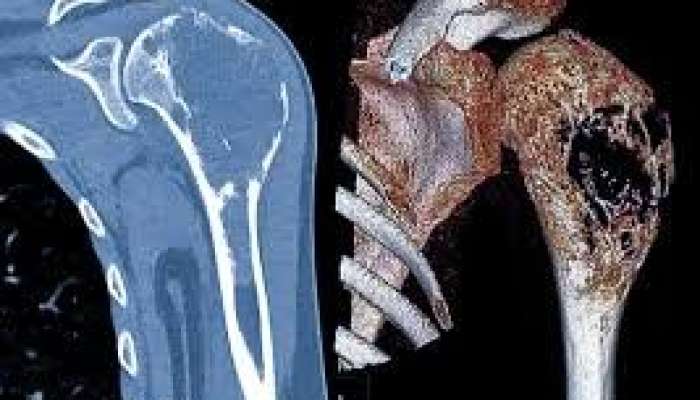

Həkimlər